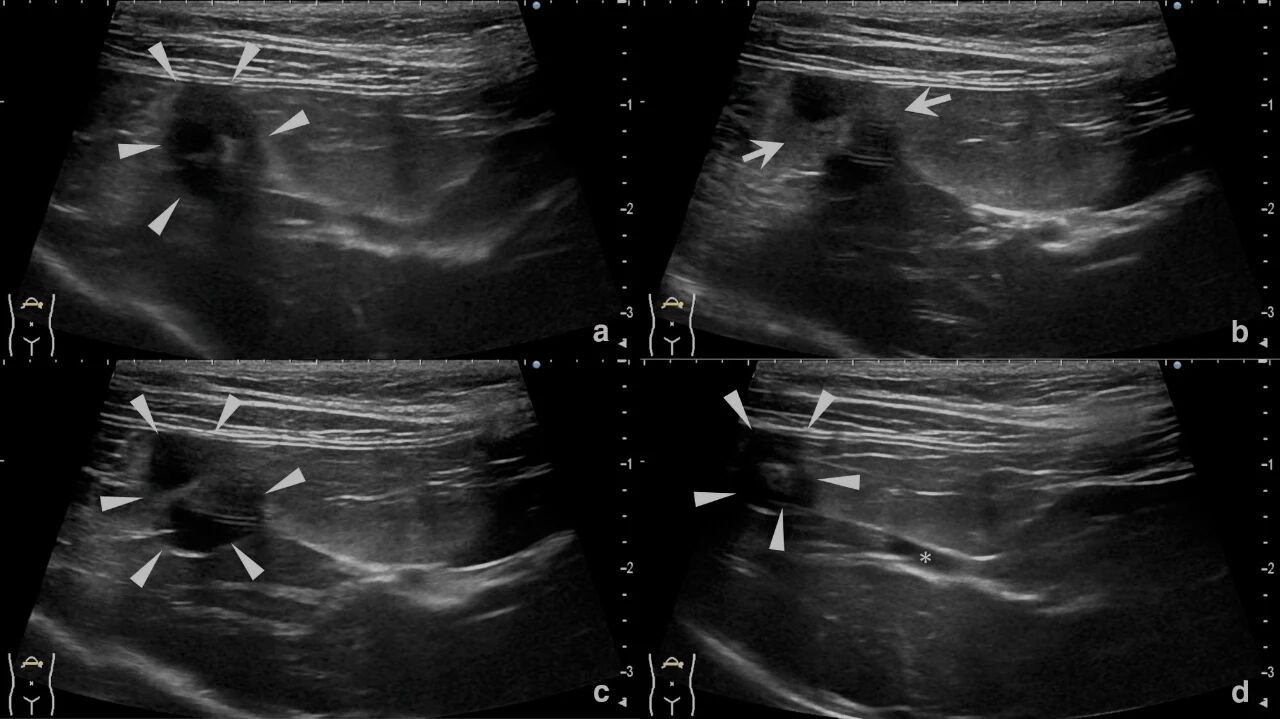

胸部及腹部X线片未见异常。腹部超声显示胆囊无扩大或壁增厚。周围脂肪局部呈高回声。胆囊体积缩小,胆囊管呈细直状,胆囊体呈连续螺旋形,交替呈现C形与反C形结构(下图)。未见胆泥、混浊或胆结石。未进行彩色多普勒评估。肝实质呈弥漫性低回声。未见肝淋巴结肿大。

↑ 超声图像。(a) 胆囊底部带有连续的C形和反C形结构(三角)。(b) 胆囊体周围的高回声脂肪(箭头)。(cd) 螺旋形胆囊体(三角);胆管看起来狭窄而直(*)。

在犬中,超声特征包括腹水、胆囊增大、壁增厚和移位,但有些病例缺乏明显特征。而本病例的超声检查结果显示胆囊较小,呈螺旋形,胆管细而直,胆囊底部不清晰,周围脂肪局部回声增强,没有出现胆囊增大、壁增厚或移位的情况,也未检测到胆囊周围积液或胆结石。尽管本病例未进行多普勒检查,但在未来病例中应考虑使用多普勒超声来评估胆囊壁的血流情况。

本病例表明,猫的胆囊扭转可能具有与其他物种不同的超声检查特征,特别是螺旋形的胆囊体和周围脂肪的高回声可能是有助于诊断的线索。需要进一步积累类似的猫病例,以明确诊断特征。

总之,猫的胆囊扭转是一种极为罕见的疾病,本病例是首次报道的无肝脏叶扭转的胆囊扭转病例。这种疾病可能表现出独特的超声检查特征,包括螺旋形的胆囊体、连续的C形和反C形曲线以及局部高回声脂肪。这些特征应促使兽医将胆囊扭转作为猫出现肝酶升高和非特异性胃肠道症状时的鉴别诊断之一。未来需要进一步研究以明确猫胆囊扭转的临床和诊断特征。